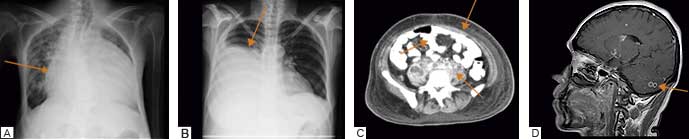

De un total de 528 pacientes que ingresaron con sospecha de serositis tuberculosa de enero del 2012 a diciembre del 2014, en 58 casos (11%) se confirmó M. tuberculosis por cultivo L-J y MGIT 960 positivo, con un crecimiento de 38 días en promedio, (34 Tb meníngea, 14 Tb pleural, 8 Tb peritoneal y 2 casos de Tb pericárdica) (figura 1). En 13 de los pacientes se practicó toma de biopsia, en los demás se omitió debido a las condiciones de gravedad que presentaban a su ingreso hospitalario. En este estudio se obtuvieron 58 controles, pacientes con cultivo para micobacterias negativo, es decir, con patología de origen no tuberculosa, de los cuales hubo 33 hombres y 25 mujeres, con un rango de edad de 22 a 65 años, la etiología correspondió a 30 pacientes con meningitis bacteriana, 4 con meningitis viral, 8 casos con derrame pleural maligno y 6 con empiema, 8 pacientes con cirrosis hepática y 2 casos con metástasis a pericardio.